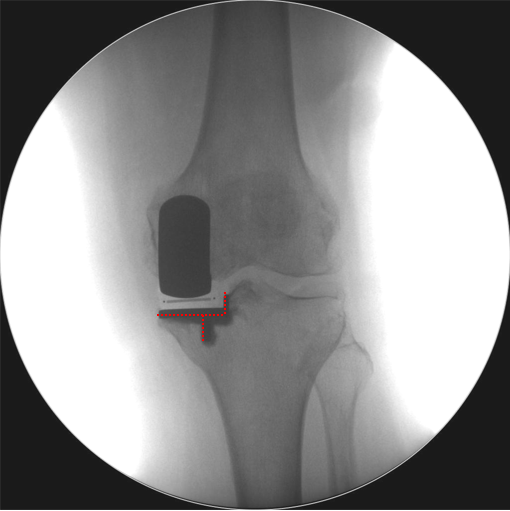

辨认bearing内的标识(透视片正位)

bearing 内的标识:点和线段“ .—. ”线段显示为“—”在前;点显示为“.”在后